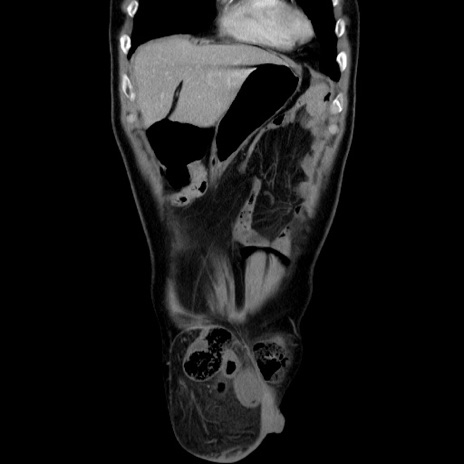

症例34(冠状断像)

【症例】60歳代 男性

【主訴】右鼠径部膨隆

【現病歴】1年程前より右鼠径部膨隆あり。自己にて還納可能だったため放置していた。3時間前より右鼠径部の脱出を認め、還納困難となり受診。

【既往歴】高血圧

【身体所見】右鼠径部に小児頭大の膨隆あり。弾性硬であり、用手還納は困難。左鼠径部にも膨隆を認める。脱出はなし。